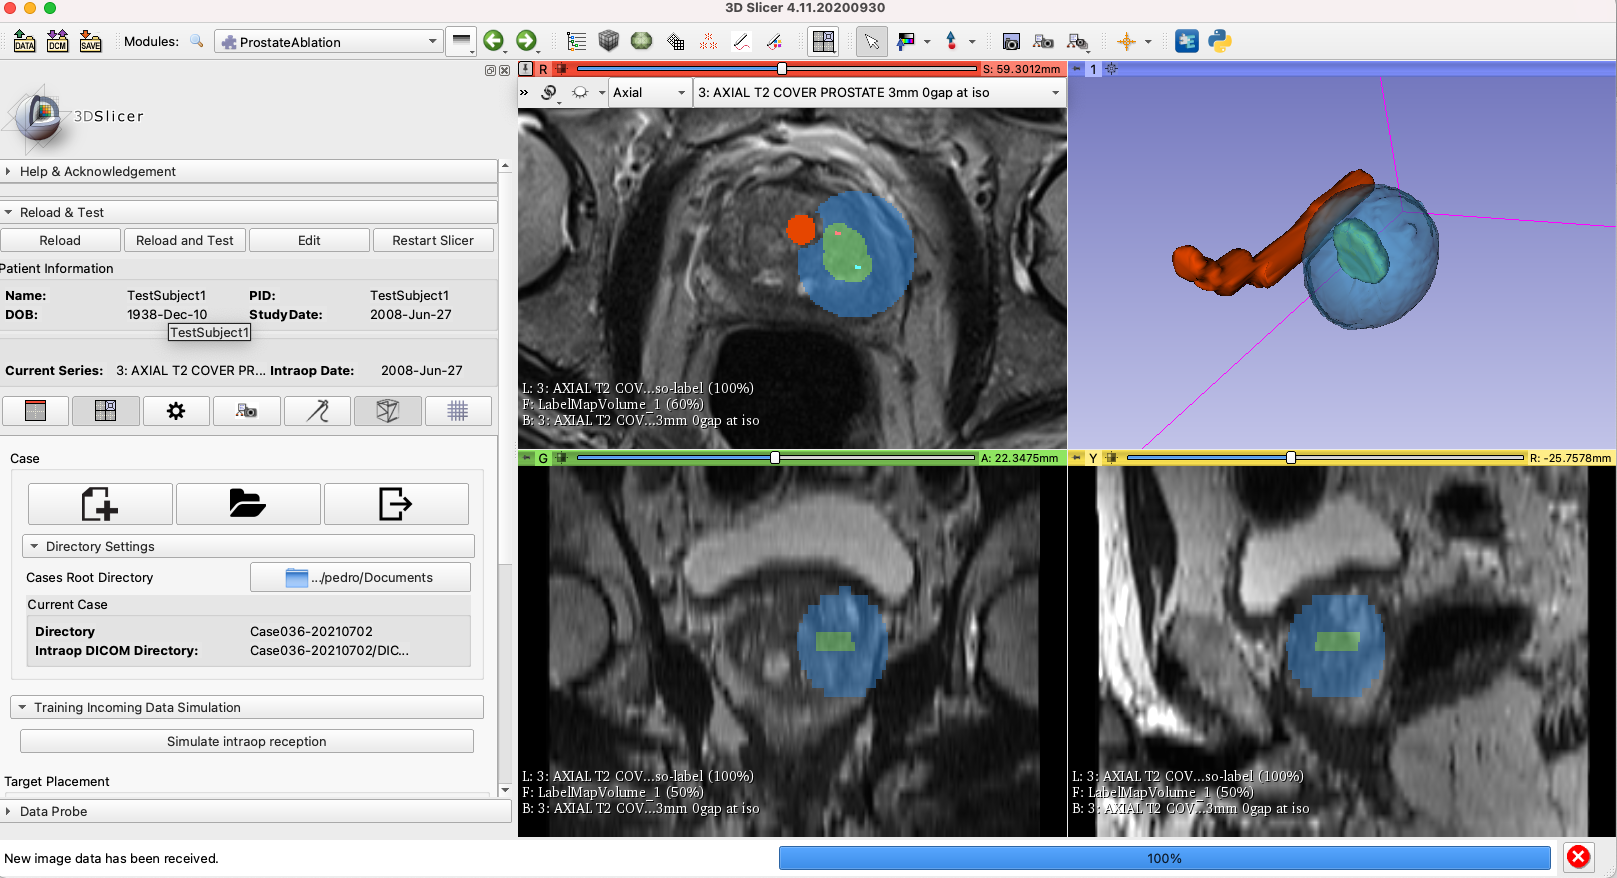

Figure 1: ProstateAblation module

Figure 3: Integration of the iceball estimation and the ProstateAblation module. the ablation target is marked in green, while the estimated iceball is in blue.

One of the advantages of the current approach is the prediction and the vizualization of the ablation margins in 3D, However, we still need to discuss the best way to vizualize the prediction and planning results. We should meet the Dr. Tuncali soon to get his input.